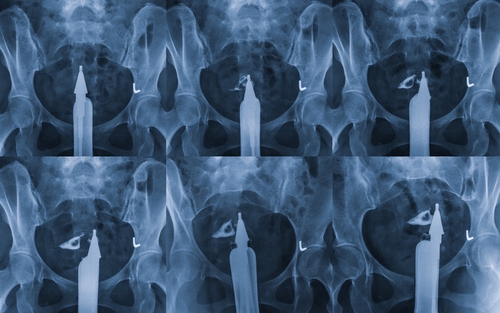

בחודש ספטמבר 2016, אישה בת 32 עם העדר הרחם המולדת (תסמונת מאייר-רוקיטנסקי-קסטר-האוזר [MRKH]) עברה השתלת רחם בבית החולים דאס קליניקס, אוניברסיטת סאו פאולו, ברזיל, מתורמת שנפטרה בשל דימום סאב ארכנואידאלי.

הווסת הראשונה התרחשה 37 ימים לאחר ההשתלה, ובאופן קבוע (כל 26-32 ימים) לאחר מכן. הריון התרחש לאחר העברת העובר הראשון הראשון 7 חודשים לאחר ההשתלה. לא זוהתה זרימת דם במהירות חריגה בדגימות של דופלר בעורקי הרחם, בטבור העובר או בעורקי המוח התיכון, ולא כל פגיעה בעובר במהלך ההריון.

לא אירעו מקרים של דחייה לאחר ההשתלה או במהלך ההיריון. הניתוח הקיסרי התרחש ב-15 בדצמבר 2017, סמוך לשבוע 36 להריון. התינוקת שקלה 2,550 גרם בלידה, המתאימה לגיל ההריון, עם ציונים של אפגר 9 בדקה 1, 10 בדקה 5 ו-10 ב -10 דקות. במעקב שבעה חודשים לאחר הלידה, התינוקת בהתפתחות תקינה ובריאה וגם האם. הרחם הוסר באותו הליך כירורגי של הלידה החיה והטיפול החיסוני הושעה.